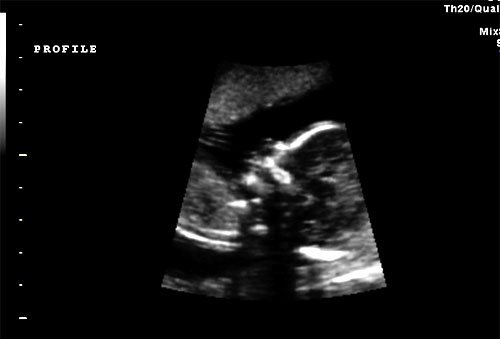

Normal 16 week 4 chamber heart |